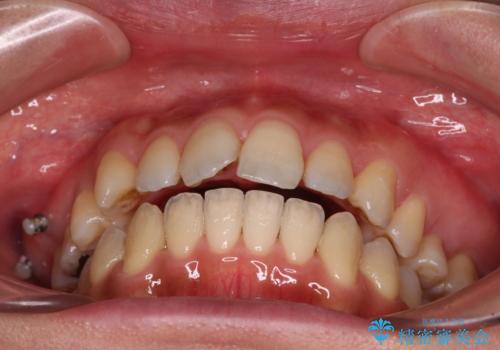

また、舌の突出癖の影響で上下前歯が接触していないオープンバイトとなっており、奥歯に負担のかかる咬み合わせとなっていました。

乳歯を抜歯し、舌側の永久歯を引っ張り出すこととしましたが、希望のインビザラインでは移動量が大きすぎて対応できない可能性があったため、ワイヤー装置にて改善することとしました。

ワイヤー装置にてある程度歯列が改善されたところで、上下をインビザラインにて矯正治療を行うこととしました。

舌のトレーニングをしっかりと行ってくださり、前歯部のオープンバイトは大幅に改善されました。